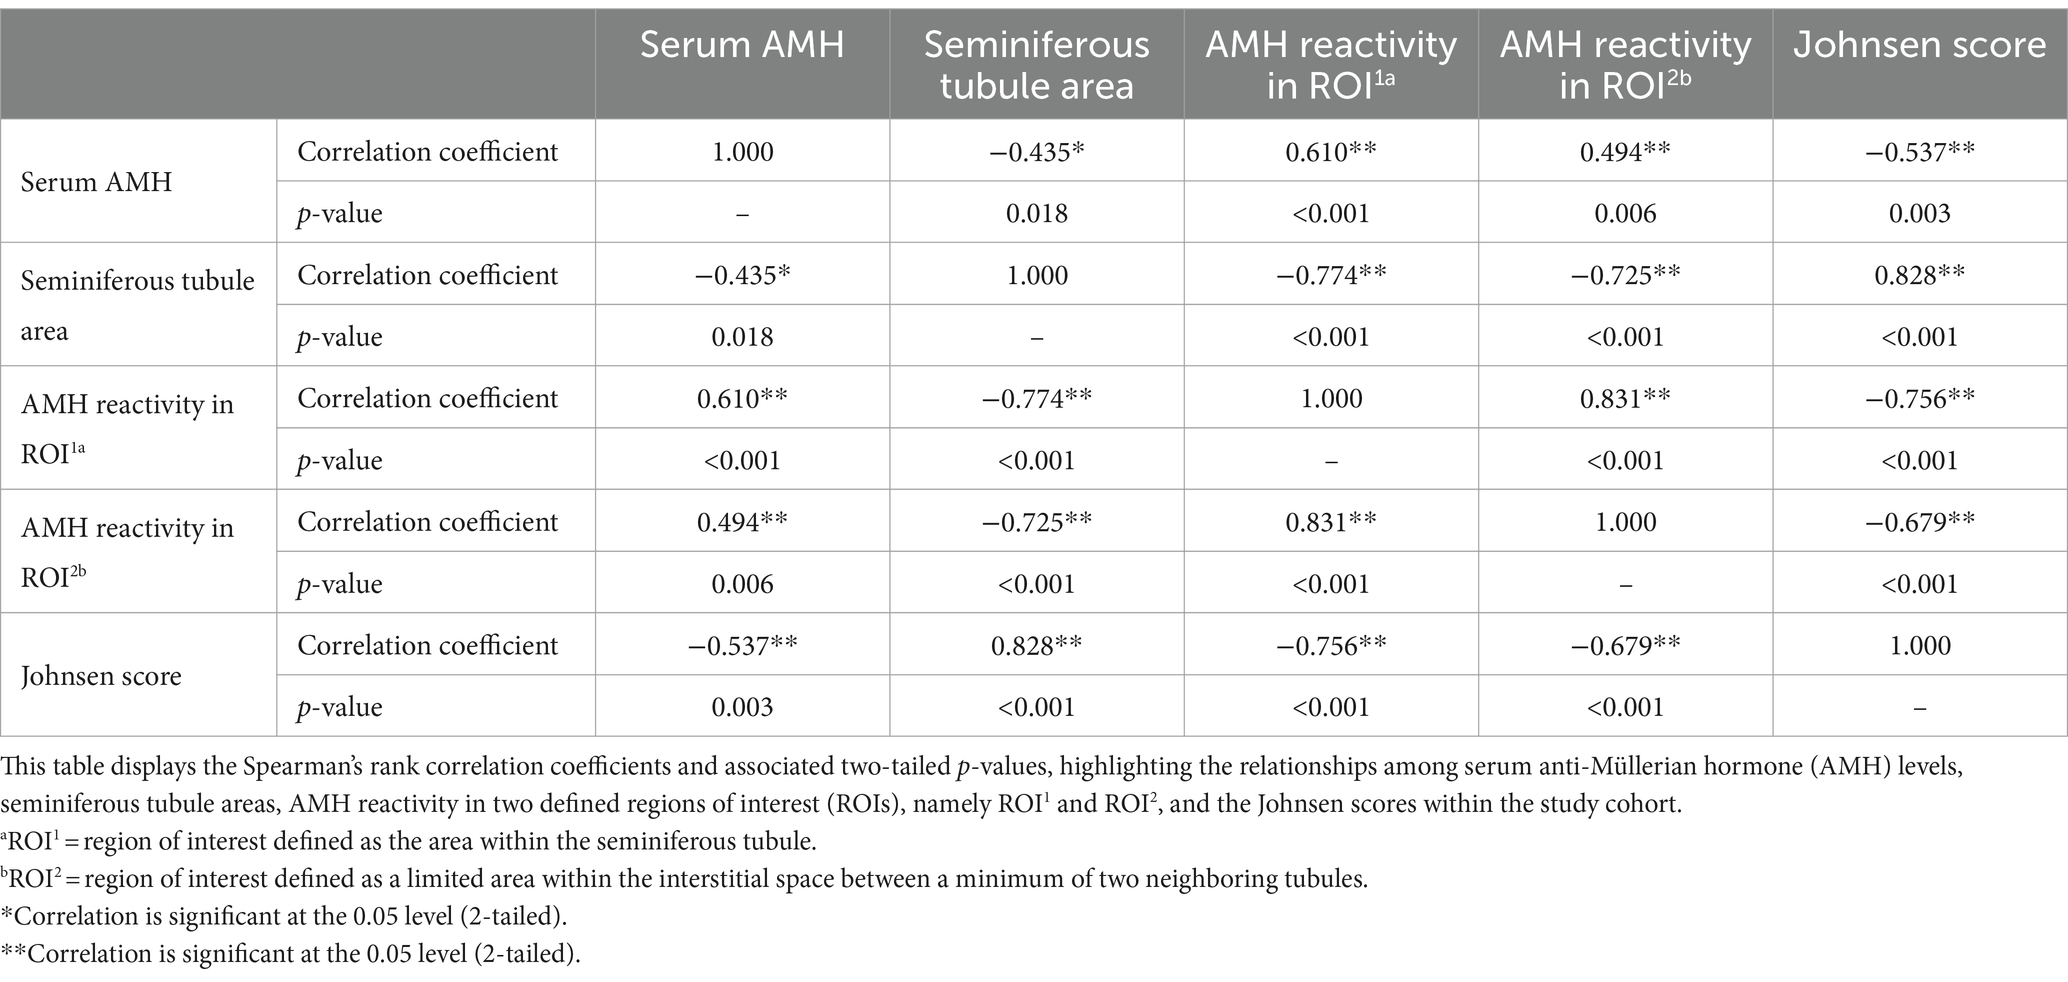

Resultados: Los niveles séricos de AMH se correlacionaron positivamente con la expresión de AMH evaluada tanto en el espacio intersticial (ρ = 0,494, p ≤ 0,01) como en los túbulos seminíferos (ρ = 0,610, p ≤ 0,001). Por el contrario, los niveles séricos de AMH mostraron una correlación negativa con el área del túbulo seminífero (ρ = −0,435, p ≤ 0,05). Las áreas de túbulos seminíferos más pequeñas se relacionaron con una mayor reactividad de AMH tanto en los túbulos seminíferos (ρ = −0,774, p ≤ 0,001) como en el espacio intersticial (ρ = −0,725, p ≤ 0,001). Además, las puntuaciones más bajas de Johnsen se asociaron con niveles séricos de AMH más altos (ρ = -0,537, p ≤ 0,01) y una expresión más alta de AMH tanto en los túbulos seminíferos (ρ = -0,756, p ≤ 0,001) como en el espacio intersticial (ρ = -0,679, p ≤ 0,001).

Curiosamente, los valores séricos de AMH se correlacionaron positivamente con la expresión de AMH tisular tanto en el espacio intersticial (ρ = 0,494, p ≤ 0,01) como en los túbulos seminíferos (ρ = 0,610, p ≤ 0,001). Por el contrario, los túbulos seminíferos más pequeños se asociaron con una mayor reactividad a la AMH en ambos ROI (túbulo seminífero: ρ = −0,774, p ≤ 0,001; espacio intersticial: ρ = −0,725, p ≤ 0,001). Del mismo modo, las puntuaciones de Johnsen disminuyeron a medida que aumentaba la expresión de AMH tisular en los dos compartimentos analizados (túbulo seminífero: ρ = −0,756, p ≤ 0,001; espacio intersticial: ρ = −0,679, p ≤ 0,001). Todas las correlaciones entre las variables analizadas se presentan brevemente en la Tabla 2.

Tabla 2. Matriz de correlación de rangos de Spearman de las variables analizadas.